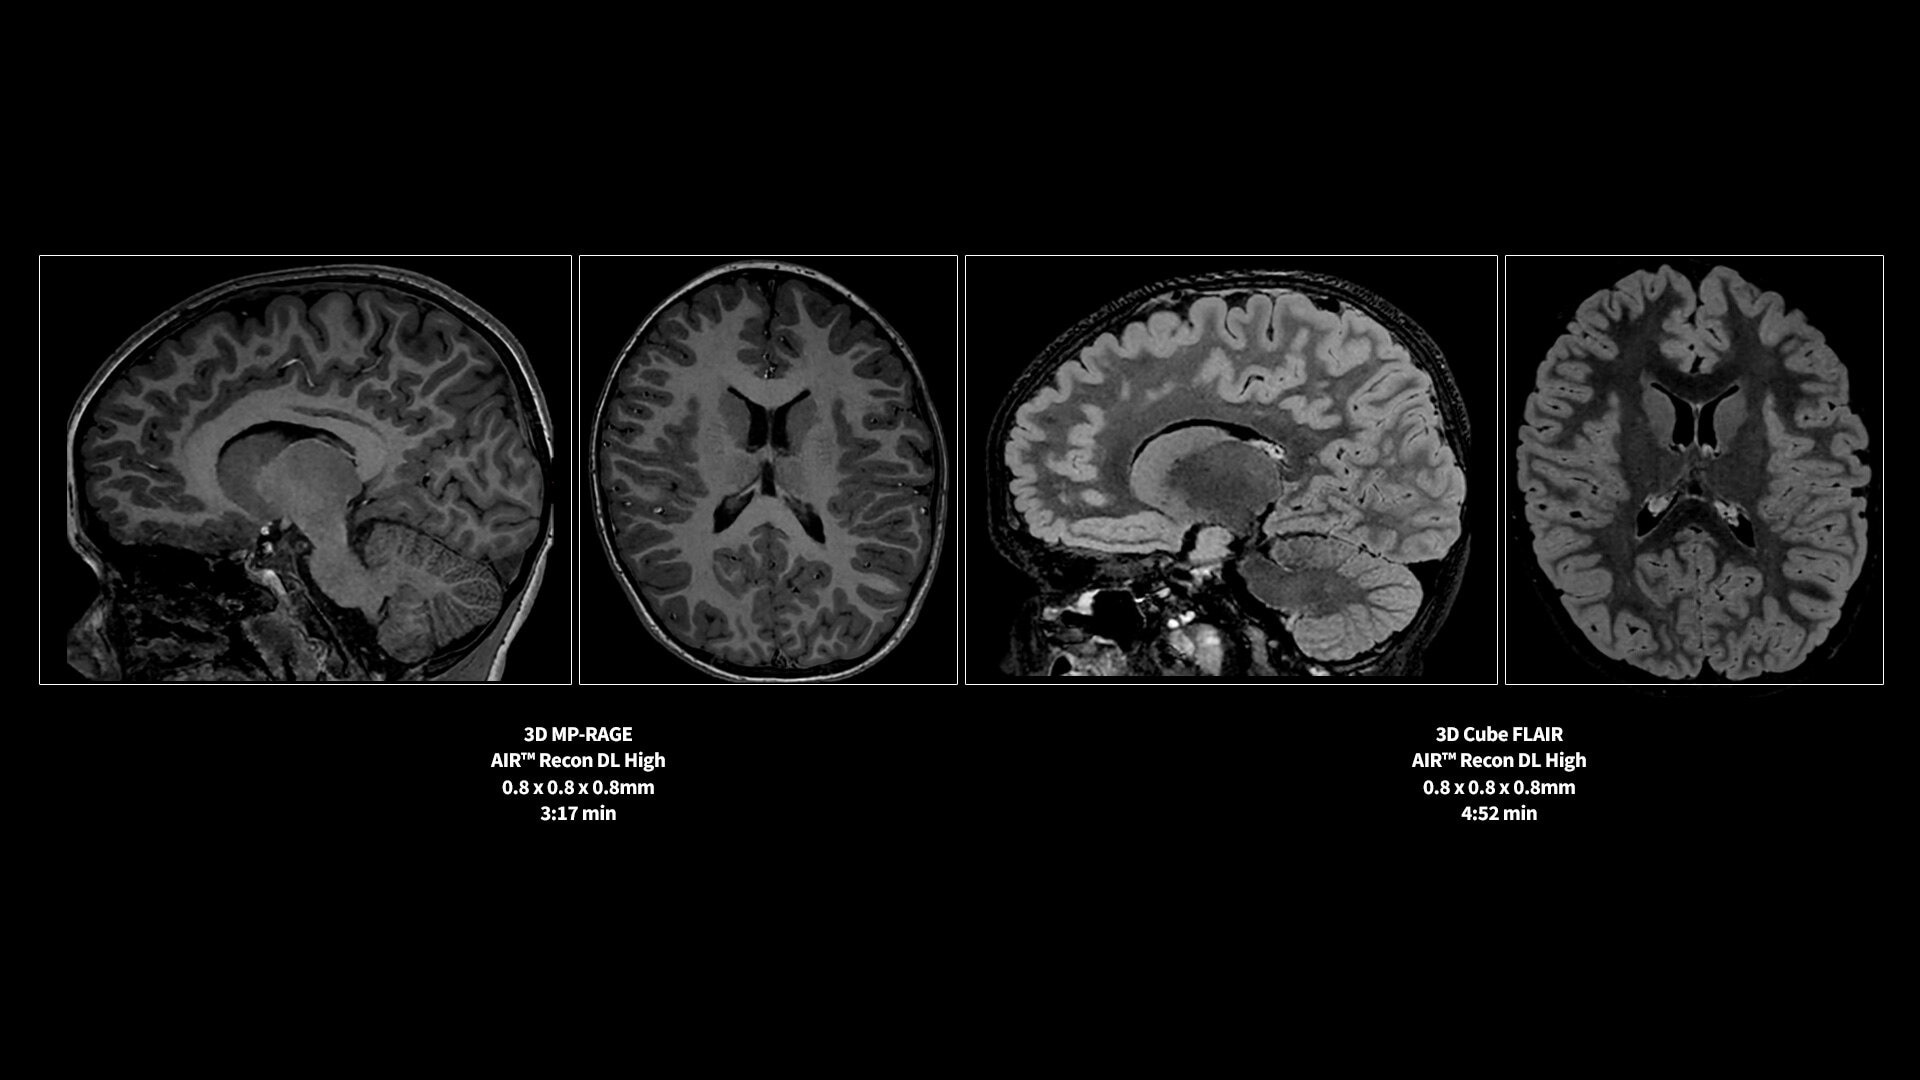

<p>AIR Recon DL</p>

Learn more ico-caret-right

GE HealthCare’s AIR x deep-learning prescription tool for automated slice placement ensures consistent image setup across follow-up exams and patients. Effortless DL reconstruction with AIR Recon DL reduces noise and scan time up to 50%, while improving SNR.

MR image reconstruction with AIR Recon DL

Evolve your MRI scanner's capabilities: experience exceptional image quality without compromising scan time.